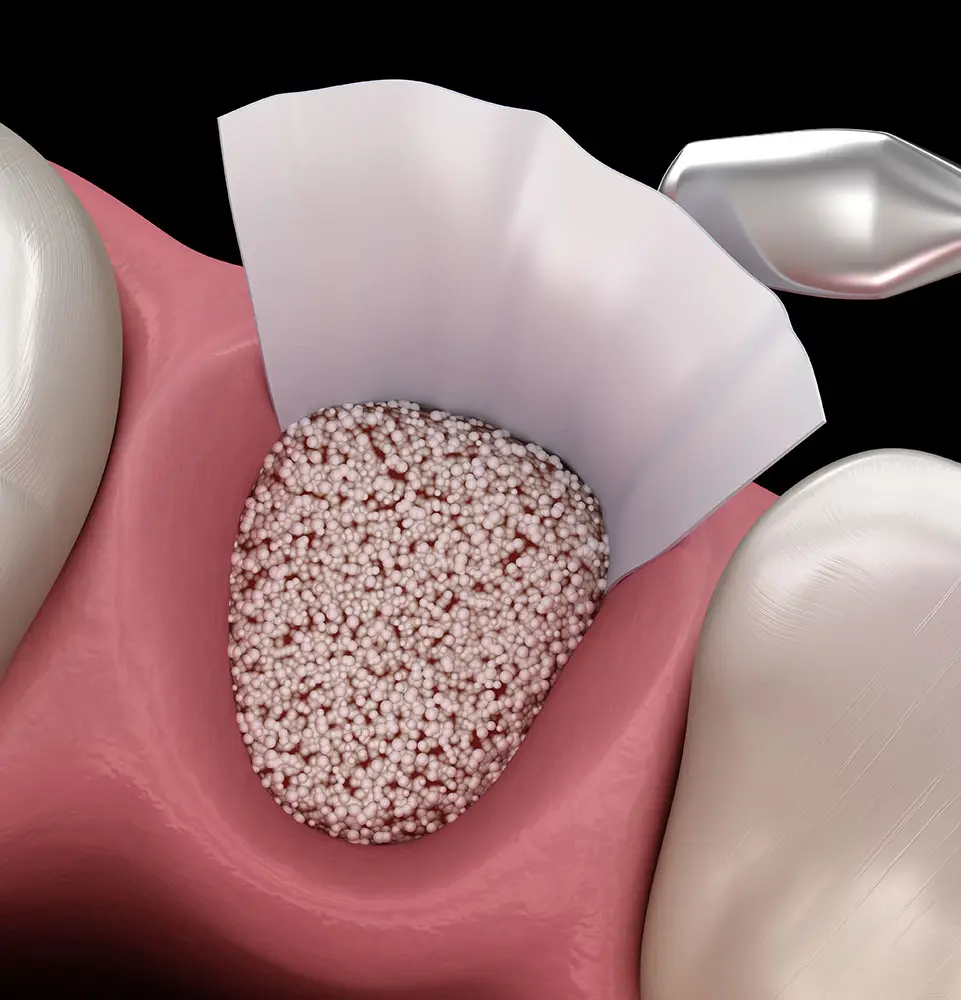

When a tooth is lost, the body no longer has a reason to maintain the bone structure that once supported it. This gradual bone loss can trigger a cascade of problems, including adverse effects on neighboring teeth, alterations to facial appearance, weakened jawbone integrity, and potential strain on the jaw joints.

Restoring the lost bone in most cases may be necessary to lay the foundation for reconstructing your smile. Bone grafting provides a solution by enabling us to augment the hard tissue within a tooth socket or reshape the bony ridge, ensuring a solid foundation for further dental work.

We frequently recommend platelet-rich plasma following tooth extractions or cyst removals to repair defects, prevent dry sockets, and stabilize the bone tissue. As a supplement to traditional bone grafting, platelet-rich plasma improves outcomes and ensures you’ll get the best final result from your treatments, including dental implants.

The process starts by taking a small blood sample. We isolate specific compounds from your blood, enhancing healing and promoting new bone tissue growth. Bone grafts with platelet-rich plasma heal faster, more comfortably, and with superior density.